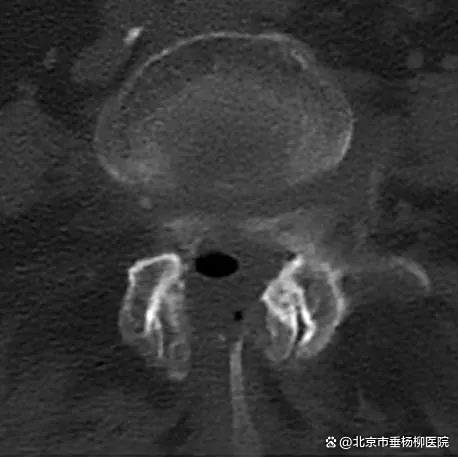

经过3个小时的手术,患者手术顺利,椎体内骨水泥弥散良好,椎管内神经减压彻底。术后患者恢复良好,当天即感觉疼痛缓解。经过2天的术后治疗,患者已经可以正常行走。术后3天,患者平安出院,后续接受康复治疗。

▲术后CT,椎管狭窄较前明显好转